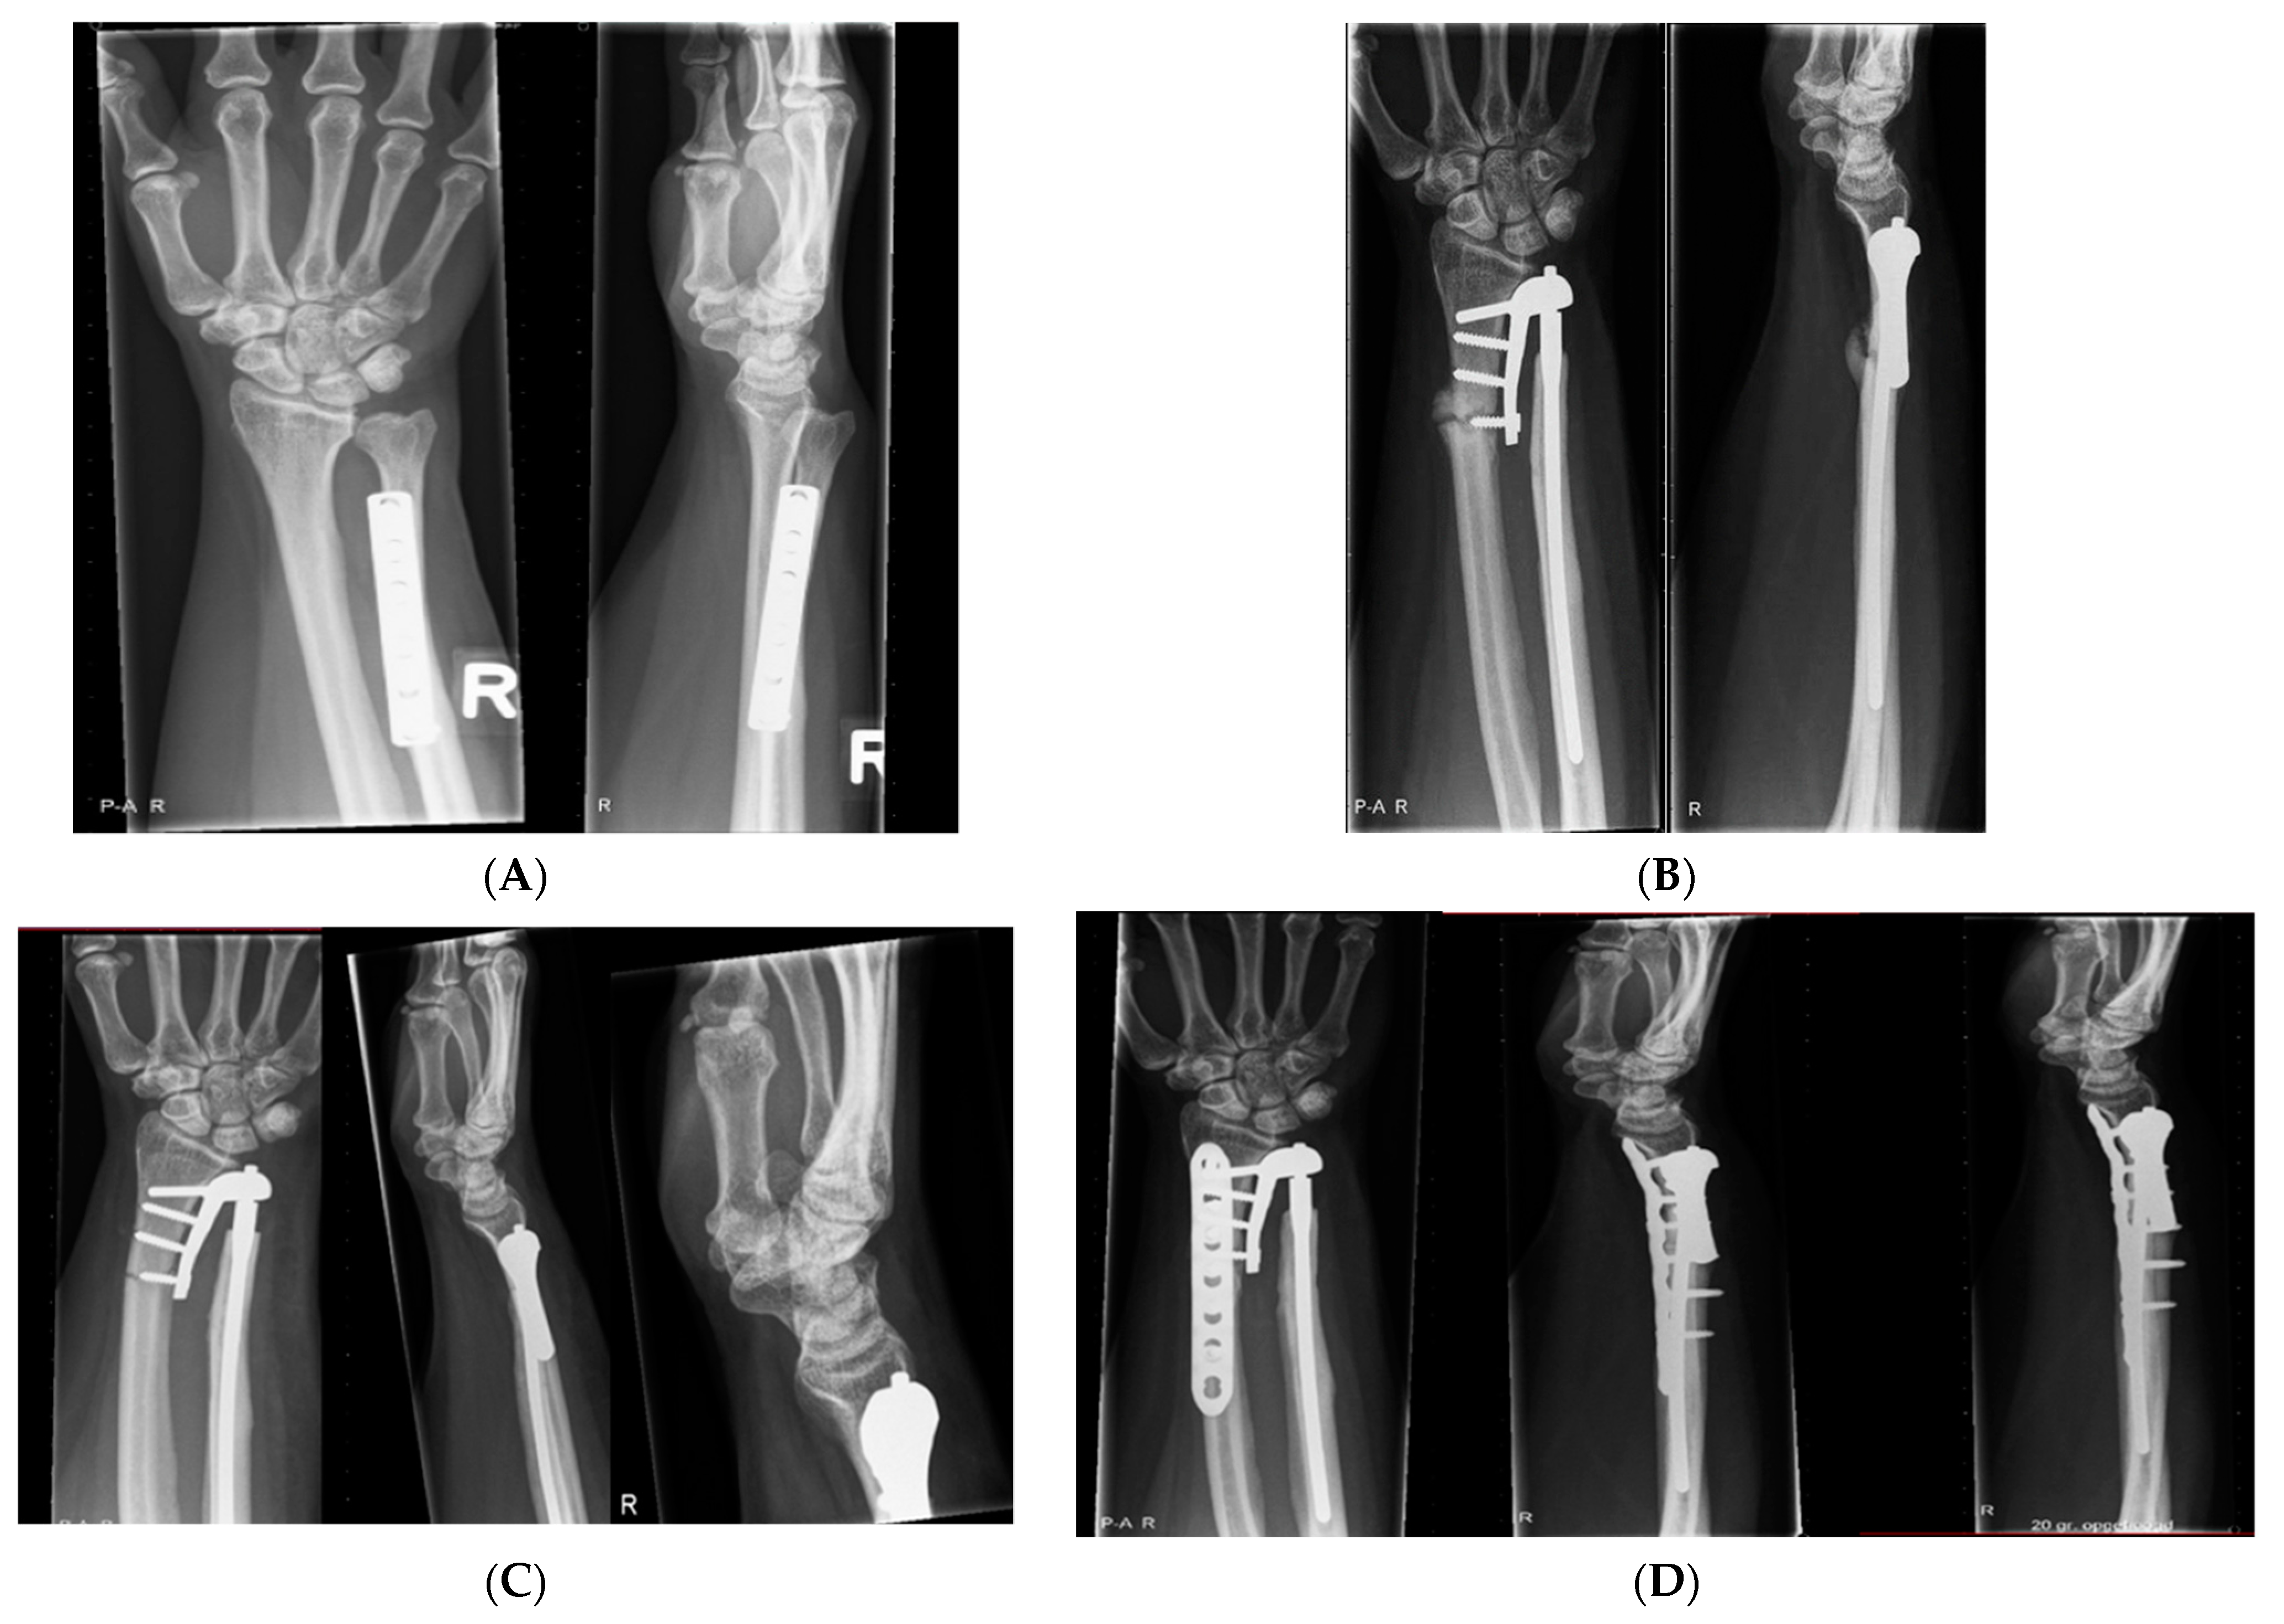

2.5. Radiographic Assessment

3.3. Radiological Evaluation

| Case | Radiological Evaluation | Combined Error | Translation Healthy | Translation Aptis | Δ Translation |

|---|---|---|---|---|---|

| 1 | Periprosthetic fracture; proximal screws | 11 | 1.5 | 0.5 | −1.0 |

| 2 | Lucency distal screw (37) | 6 | 2.8 | 0.6 | −2.2 |

| 3 | Heterotopic ossification (8) | 7 | 1.3 | 0.2 | −1.1 |

| 4 | No abnormalities | 5 | 2.8 | 0.5 | −2.3 |

| 5 | Heterotopic ossification (4) | 12 | 2.7 | 3.5 | 0.8 |

| 6 | - | 7 | 1.4 | 4.1 | 2.7 |

| 7 | Heterotopic ossification (5) + Lucency distal screw radius (13) | 14 | 2.1 | 0.3 | −1.9 |

| 8 | No abnormalities | 6 | 1.6 | 0.3 | −1.3 |

| 9 | Chip distal ulna (7) + Heterotopic ossification (24) | 13 | 1.8 | 0.3 | −1.5 |

| 10 | Dystrophic calcification (1.5) | 10 | 2.4 | 0.4 | −2.0 |

| 11 | Lucency distal screw (8) + heterotopic ossification (48) | 10 | 1.9 | 2.0 | 0.1 |

| 12 | Heterotopic ossification (57) | 9 | 1.7 | 0.3 | −1.4 |

| Average (SD) | 9 (3) | 2.0 (0.6) | 1.1 (1.3) | −0.9 (1.4) |